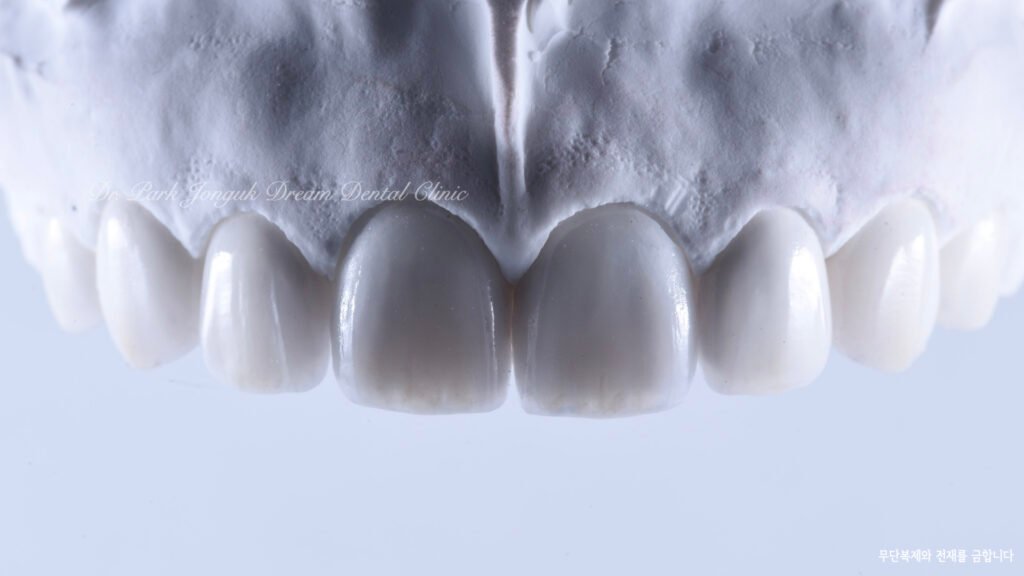

사진 8~10 — 최종 라미네이트 제작

드림치과에서는 ‘빌드업(Hand-Layered)’ 방식을 적용합니다.

단일 세라믹이 아닌 여러 종류의 세라믹을 층층이 쌓아

자연치아 고유의 깊이감과 투명한 끝부분을 재현합니다.

결과적으로 환자의 치아는 투명하고 자연스러워졌으며,

표면의 반사와 색조 변화가 자연치아와 구별되지 않을 정도로 일체감 있게 완성되었습니다.